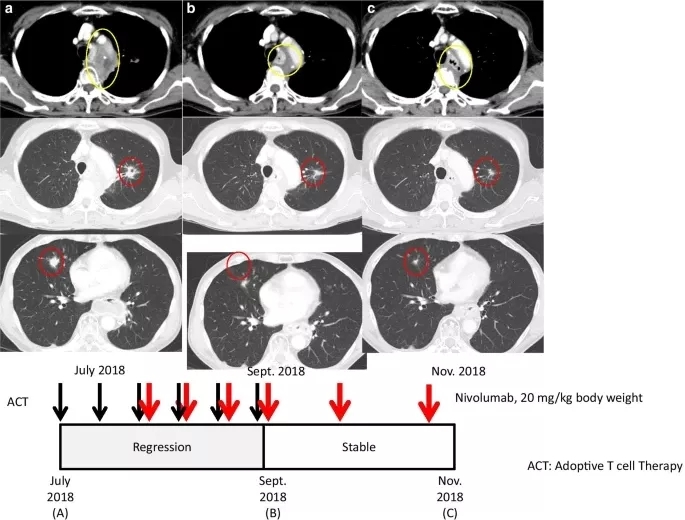

病例1

日本女性患者,于2016年2月被诊断为食管癌,时年66岁。活检和CT显示食管鳞状细胞癌临床Ⅳ期(UICC, T4N2M0)。2016年3~4月接受氟尿嘧啶/铂同步放化疗(CCRT),随后于2016年6月行食管次全切除术。手术肿瘤标本的组织病理学分析显示,食管癌处于临床Ⅱ期(UICC, T3N0M0)。2016年11月常规CT示左肺新发肺结节及纵隔淋巴结肿大,直径2.0 cm。

2016年12月因肺淋巴结转移放疗开始后就诊,并于2017年1~2月接受ACT治疗。在放疗期间,至2017年4月,患者以2~3周为间隔接受了4次αβT淋巴细胞的ACT治疗,随后患者使用氟尿嘧啶/铂/多西他赛化疗直至2018年1月。然而,2018年2月常规CT显示多发性肺转移。

2018年7月,患者报名参加了作者所在医院的一项临床试验(临床试验编号UMIN000028756)(图1a)。在开始临床试验前,作者团队利用患者的肿瘤标本评估了PD-L1表达水平,发现肿瘤组织中PD-L1表达水平小于1%。肿瘤微卫星不稳定(MSI;数据未显示)。患者以2周为间隔接受2次ACT治疗,随后以0.3 mg/kg体重的剂量接受纳武利尤单抗治疗,以2周为间隔接受4次ACT治疗,作为诱导治疗的一部分。

2018年9月19日(纳武利尤单抗启动后9周)的随访CT扫描显示部分缓解,肺转移灶和纵隔病变体积减少48%(图1b)。患者继续接受剂量为40 mg/kg体重的纳武利尤单抗作为维持治疗(时间间隔为3周)。2018年随着患者的临床进程,X线拍片显示有轻微改善(图1c),由于患者临床状态良好且存活,因此继续应用纳武利尤单抗维持治疗。患者有轻微但无症状的甲状腺功能减退,需要补充甲状腺激素,然而患者并没有显示其他临床显著的治疗相关毒性。

图1. 病例1的临床病程

轴位CT图像对应于治疗和疾病状态的时间线。黄圈表示纵隔病变,红圈表示肺转移病灶。a.(上)使用纳武利尤单抗治疗前的状态。b. 过继细胞治疗(ACT)和免疫检查点抑制剂(ICI)联合治疗后纵隔和肺转移灶的消退。在ICI维持治疗期间,反应持续(c)。黑色和红色箭头分别表示ACT和纳武利尤单抗给药(下)。